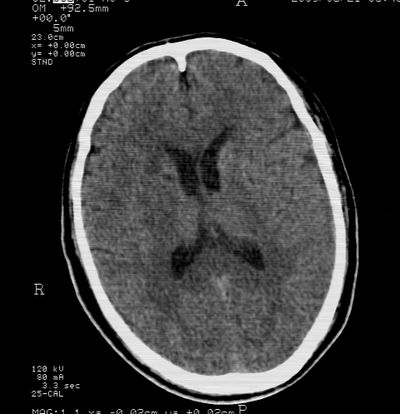

标题: CT21793:李x,男,62岁,头疼,头晕,家属否认有出血病史, [打印本页]

标题: CT21793:李x,男,62岁,头疼,头晕,家属否认有出血病史,

右枕叶.右侧脑室前角旁脑梗塞

右基底节,海马并侵及右枕,左枕叶梗塞

右枕叶.右侧脑室前角旁脑梗塞。

支持多发脑梗塞

支持右基底节,海马并侵及右枕,左枕叶梗塞。

支持右基底节,海马并侵及右枕,左枕叶梗塞。建议增强。

多发性梗塞

多发梗塞,左小脑软化灶

多发性脑梗塞。

考虑多发脑梗塞,建议mri检查。